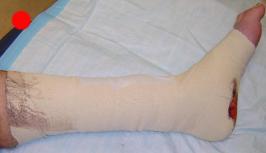

Postoperative (12th) images of left ankle

The images displayed here were created at various appointments following surgery performed by Dr. Daniel Saunders. In the X-Ray you can see

where Dr. Saunders has removed the fibula plate, joined the tibia and fibula with a screw, built-up the area of the tibia where previously

there was considerable absence of bone and lastly added the EBI OsteoGen-M Bone Stimulator (dual lead). The photos show the left side site

where the fibula plate was removed, the top site where donor bone, bone filler material and the stimulator were added and the right side

where the tissue has burst because of swelling. Liam was placed on an IV drip of Vancomycin following surgery to combat the potential onset

of Osteomyelitis. The image of the cast includes the fibula plate that was removed during surgery. The next images were taken later and show

that the staples and stitches were removed. In one of the images, you can see Liam's wife Madeline helping with leg cleanup and in one image

can be seen the EBI representative after being put to work (holding up the left leg while the latest cast cures) by Dr. Saunders. Later shots show

a healing tissue burst site with some overgrowth and Dr. Saunders cauterizing the overgrowth. Bones shifting too much (shown in X-Rays). The

last images are of the left ankle prior to the 13th surgery.